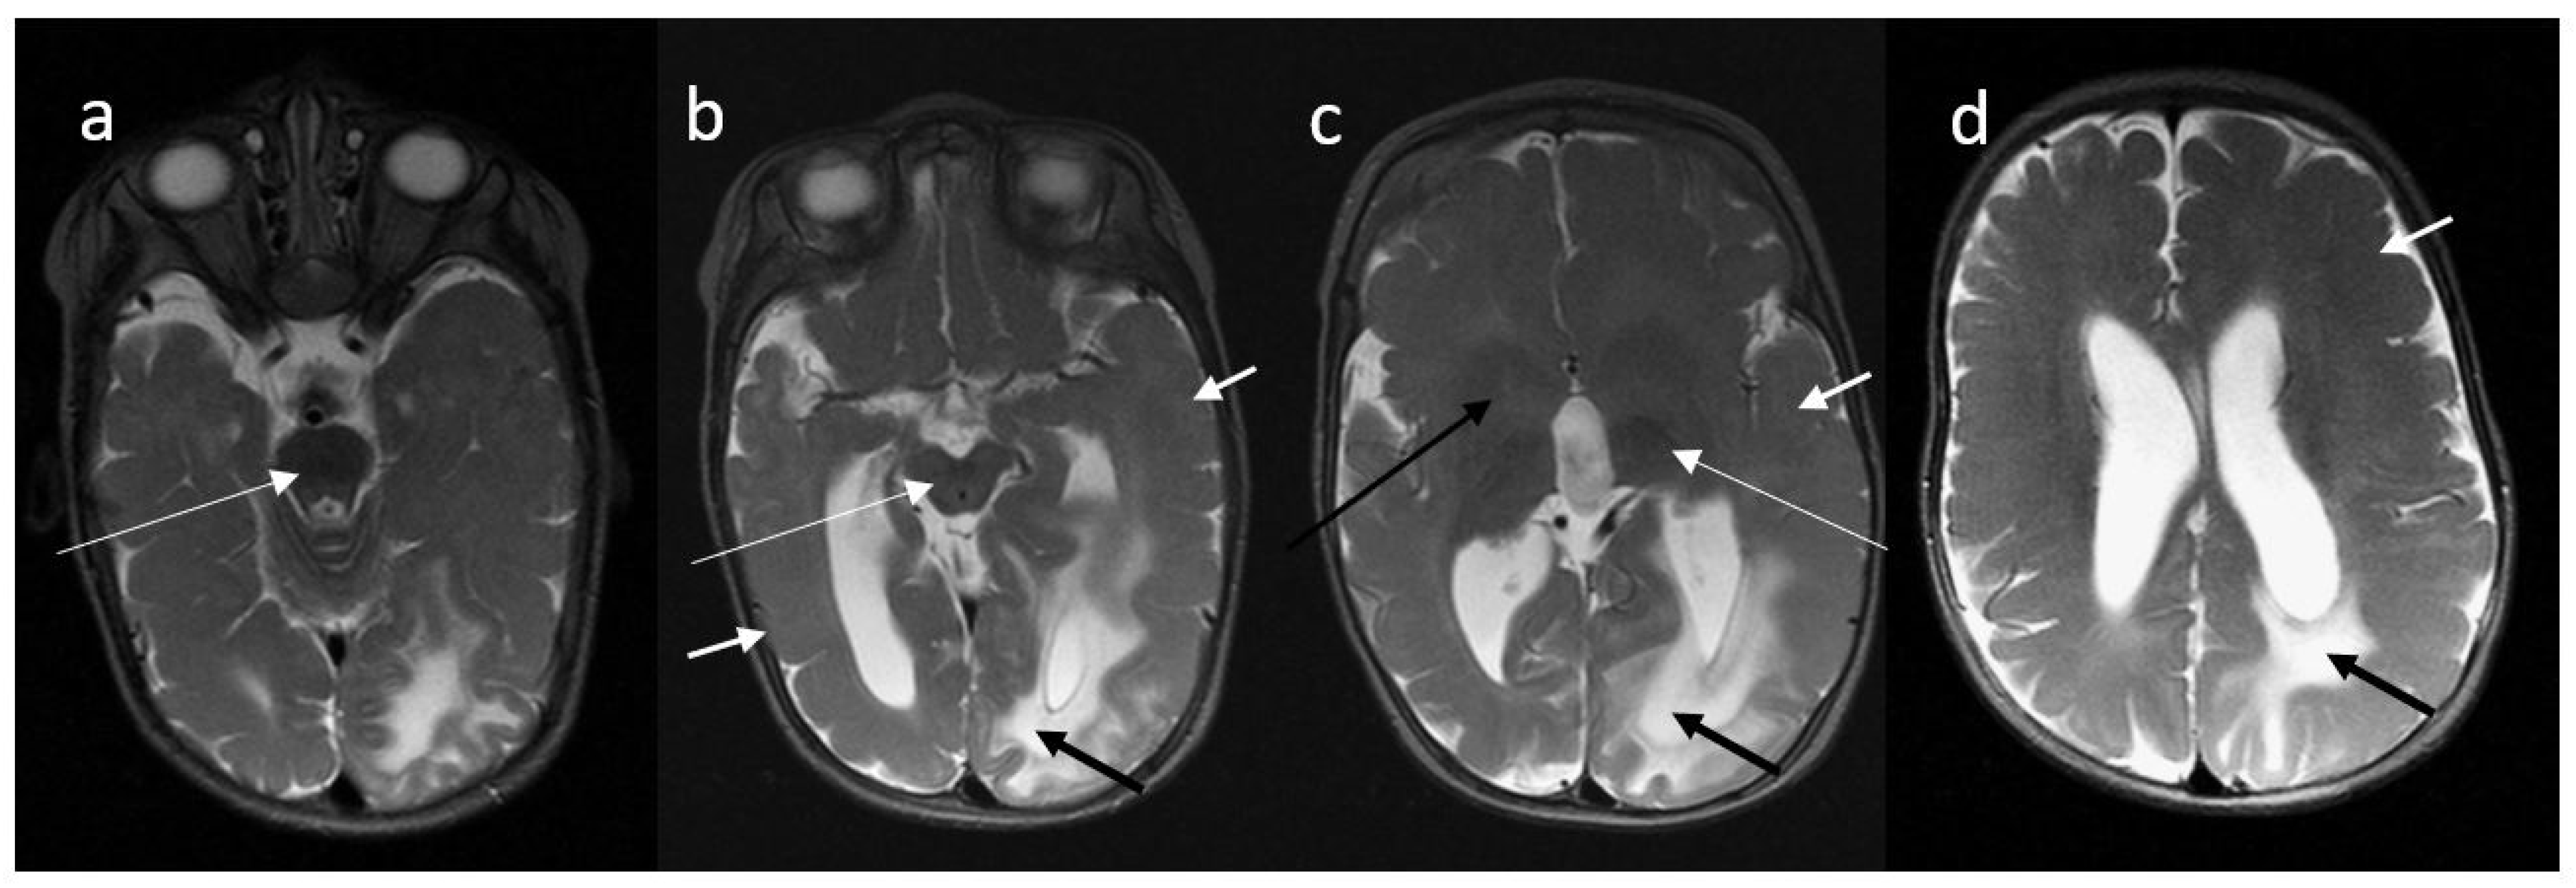

A brain MRI scan performed at the age of 9 months revealed left-sided hemimegalencephaly, generalized cortical dysplasia with polymicrogyria and pachygyria, hypoplasia of the midbrain and brainstem, and delayed myelination (Figure 1).

A 9-month-old boy, MR brain examination, (a–d)—axial T2-weighted images. T2-weighted images in axial plane demonstrate asymmetry of the cerebral hemispheres with the left one slightly larger than right. Diffuse loss of sulcation, broad gyri in association with diffuse polymicrogyria/pachygyria and indistinct gray–white matter differentiation are seen in both cerebral hemispheres (short white arrows on (b–d)). Lack of white matter myelination: weak myelination is visible only in posterior limbs of the internal capsules (long white arrow on (c)) and brainstem (long white arrows on (a,b)) and cerebellar peduncles (not shown). Basal ganglia show abnormal appearance bilaterally (long black arrow on (c)). The white matter of the left occipital lobe and posterior part of left parietal and frontal lobes is abnormally hyperintense on T2-WI (short black arrows on (b–d)). Brain stem (long white arrows on (a,b)) and splenium of the corpus callosum are hypoplastic. The lateral ventricles and third ventricle are enlarged.